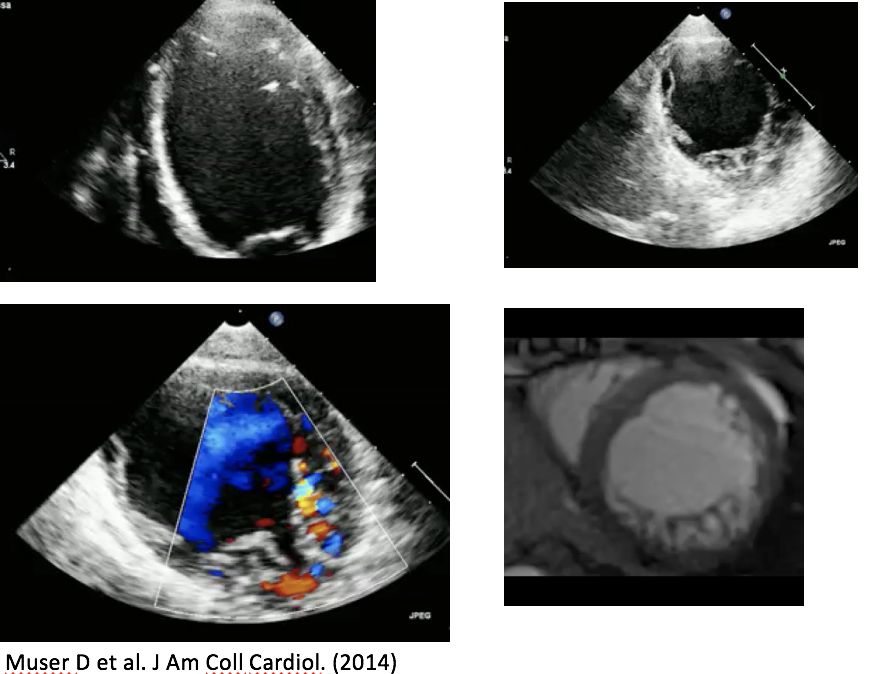

• 2016年Daniele Muser在Heart Rhythm发表了9例LVNC患者导管消融的随访结果

• 89%患者合并心功能不全(mean EF 40±13%),对合并室速患者进行电解剖标测提示电压基质不正常区域与术前MRI及超声检查的非致密化区域吻合

• 在平均4年及平均1.8±1.1次消融治疗后, 1例(11%)患者仍有室性心律失常发作. 在4/8 (50%)患者中观察到左室收缩功能改善.

• 没有患者死亡或进行心脏移植

Daniele Muser etal.hrthm.2016.11.014